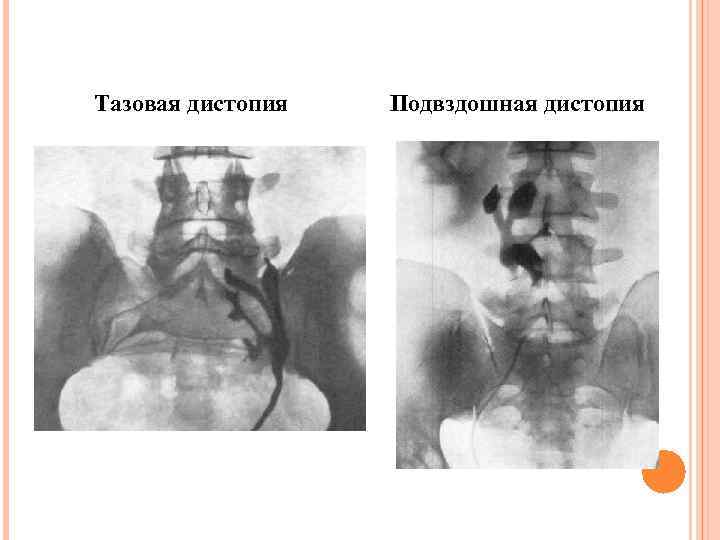

Тазовая дистопия Подвздошная дистопия

Тазовая дистопия Подвздошная дистопия